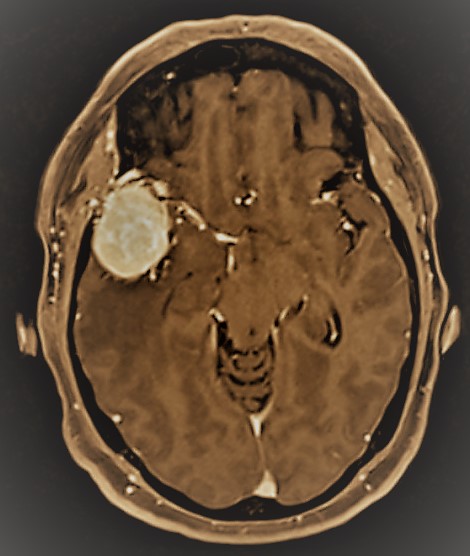

–Meningiomas: Se trata del tumor cerebral benigno más frecuente. Su origen se sitúa en una de las capas meningeas que rodean el cerebro, en concreto la aracnoides. En un 90% de los casos los meningiomas corresponden al grado I de la clasificación de la Organización Mundial de la Salud (en adelante OMS) lo que les confiere un comportamiento biológico benigno. Muy raros en niños, son más frecuentes en mujeres aumentando su incidencia conforme avanza la edad. En caso de presentar síntomas, crecimiento progresivo o efecto compresivo sobre las estructuras intracraneales es preciso su tratamiento, generalmente quirúrgico. Los casos menores de 3 cm y con una localización profunda pueden beneficarse de la Radiocirugía. Aquellos casos con un diagnóstico incidental (los encontrados de forma inesperada debido a una prueba de imagen motivada por otra causa) sólo precisarán tratamiento en menos de un tercio de los casos, permaneciendo el resto estables y asintomáticos.

-Schwannomas (Neurinomas): Se trata de tumores originados a partir de las células de Schwann, encargadas de formar la mielina de los nervios ( la capa grasa aislante que los recubre y permite que puedan llevar a cabo la conducción eléctrica de los estímulos nerviosos). A nivel intracraneal la localización más frecuente de los schwannomas tiene lugar en el ángulo pontocerebeloso, donde representan el tumor más frecuente. En esta localización se originan a partir del octavo par craneal (VIII pc), esto es, el nervio vestibulococlear (o estatoacústico) encargado de la audición y el equilibrio. Es, por ello, muy frecuente que la pérdida de audición unilateral sea el síntoma inicial que conduzca al diagnóstico. El tratamiento de elección es la cirugía, si bien aquellos menores de 3 cm puden estabilizarse gracias al tratamiento con Radiocirugía.